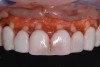

Fig 1. Example of a patient with a gummy smile.

Figure 1

Past and recent studies suggest that high smile lines (Figure 1) are present in a considerable amount of the adult population,1 possibly affecting up to about 29% of patients.2 In a previous article (Part 1), the authors proposed a revised classification of the possible causes of gummy smile (GS) and short tooth syndrome (STS) and suggested a diagnostic process aimed at defining the etiological causes and correlating them to the responsible anatomical area(s).